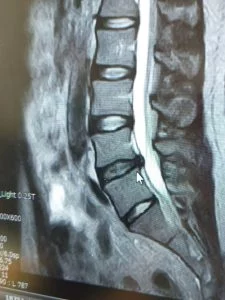

実際のMRIの画像がこちらです。

レントゲンだとここまで鮮明には映らないのですが、MRI画像だと椎間板がウニョッとはみ出した様子がよく分かります。

(※マウスポインターの矢印の位置)